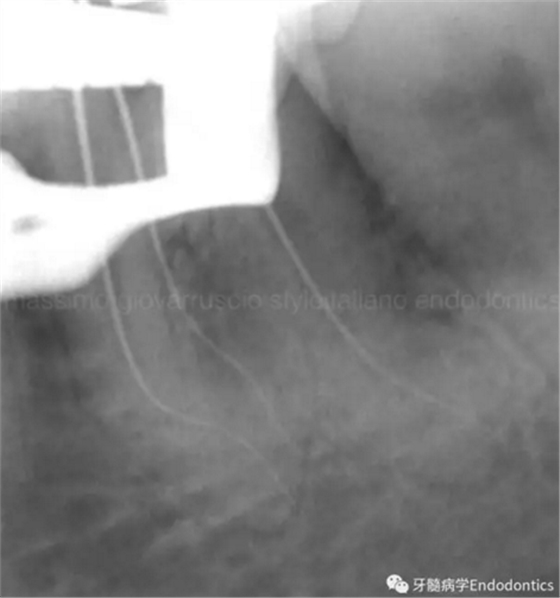

圖7.具有解剖障礙的根管,比如根尖區(qū)不規(guī)則的直根管、存在不規(guī)則急彎的彎曲根管。

圖8.這個根管需要智慧和毅力才能越過。難點(diǎn)在于通過在觸覺(通過手用器械傳來的感覺)感受到銼在根尖的阻力。這會發(fā)生是因?yàn)殇S的尖部會被不規(guī)則解剖形態(tài)干擾,而不是銼到全長并超出。

圖9.當(dāng)遇到了根尖方向的阻力,退出銼,使用銼預(yù)彎鉗(Endobender)平滑的預(yù)彎銼尖部的2mm,將銼上的硅膠止動片的方向指示調(diào)成朝向銼彎曲的方向,這樣你就可以繞過障礙形成通路了。

圖10.探查時(shí)小心地使用給手表上發(fā)條的動作使銼向前通過障礙。遇到阻礙時(shí),稍微回拉銼,將銼尖轉(zhuǎn)向新的方向,向根尖方向扭動,觀察銼是否前進(jìn)。如果沒有,將銼回拉,重新將彎曲的銼尖改變方向,觀察是否通過。不斷重復(fù),觀察是否前進(jìn),直至通路形成。必須使用根測儀和X線片檢查在障礙通過后是否到達(dá)了根尖止點(diǎn)。